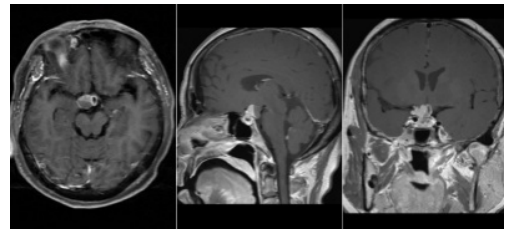

颅咽管瘤(Craniopharyngioma,CP),是位于鞍区或鞍上区的中枢神经系统良性肿瘤,其来源于胚胎残存组织。主要临床症状:视觉障碍(视力下降、视野缺损)、颅高压症状(头疼、恶心呕吐)、内分泌功能障碍(乏力、停经泌乳、尿崩、发育迟滞、性功能下降等)、下丘脑损害症状(行为变化,昼夜节律不规律,渴感消失)等,发病率:约占颅内肿瘤的6%~9%,占儿童鞍区肿瘤的54%,人群年发生率为1.3/100万。颅咽管瘤不但不是罕见疾病,而且是一种儿童较为常见的颅内肿瘤。手术是治疗颅咽管瘤的主要手段。颅咽管瘤虽然是良性肿瘤,但位置深在,毗邻重要神经血管结构,部分患者手术难度较高,在神经外科手术技术上,被称为皇冠上的明珠。

本患者肿瘤位于鞍内及鞍上区域,呈囊实性,与下丘脑粘连紧密,伴钙化明显,视神经、垂体柄受压移位明显,毗邻重要神经血管结构,手术难度较高,术中早期瘤体中心减压可以为肿瘤的包膜外分离提供空间,尤其是一些囊性成分的减压。对蛛网膜平面进行锐性和轻柔的分离是非常重要的,可以避免供应视交叉的垂体上动脉分支血管的损伤。术中选用成角内镜可以进一步观察和切除直视下难以到达的角落里的残余肿瘤。术前通过影像学表现判断垂体柄的位置,术中根据垂体柄与肿瘤的关系,尽可能多地或完整地保留垂体柄,可减轻术后尿崩症的发生率。本患者术中视神经、垂体柄、穿支血管保护完好,肿瘤完全切除,术后患者视力下降、乏力等症状明显改善,无垂体功能低下、脑脊液鼻漏、颅内感染等并发症,患者生活质量得到很大改善,患者家属满意度较高。目前,经鼻蝶微创手术成为颅咽管瘤的主要手术方式,减少手术创伤,缩短手术时间及住院时间,也为患者降低了经济负担。